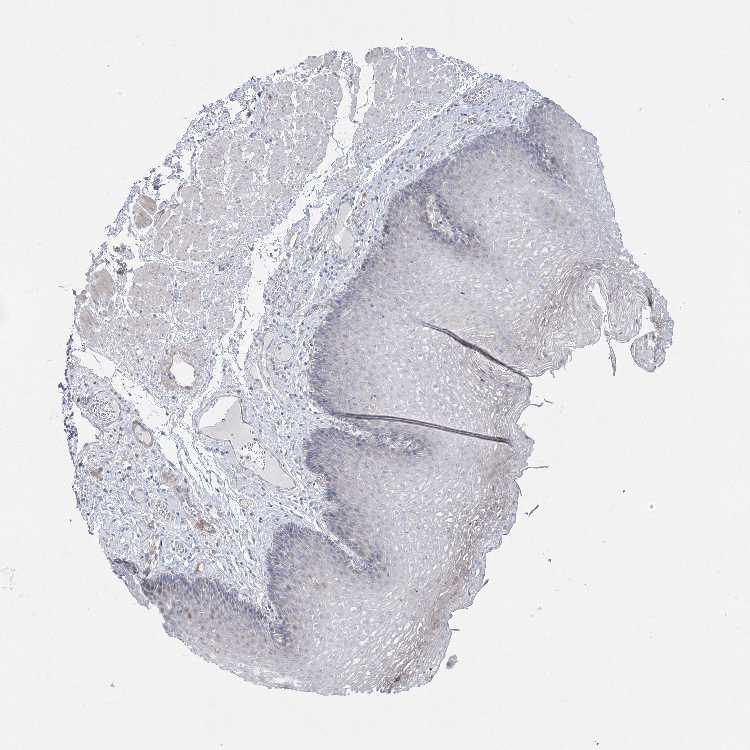

ESOPHAGUS - Antibody stainingi

Antibody staining in the annotated cell types in the current human tissue is reported as not detected, low, medium, or high, based on conventional immunohistochemistry profiling in selected tissues. This score is based on the combination of the staining intensity and fraction of stained cells.

Each image is clickable and will lead to virtual microscopy that enables deeper exploration of all samples and also displays staining intensity scores, fraction scores and subcellular localization as well as patient and tissue information for each sample.

Antibody HPA032148Antibody HPA057356

Squamous epithelial cells Not detectedNot detected